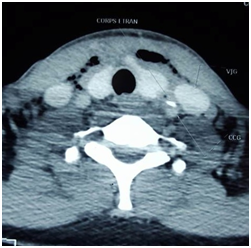

Case 2: A 24-year-old man complaining of torticollis, and dysphagia, evolving for 6 days. The patient reported ingestion of fish bone. The clinical examination founded, hypersialorrhea, a painful cervical node. X ray showed the foreign body (Figure 3). The extraction of the fish bone (Figure 4), the drainage of abscess and the trimming of the oesophageal wound were done by external surgical approach. During the extraction the carotid was notched. One month later, clinical and radiological examination were normal.

Figure 3 C-ray shwed foreign body at c6c7.